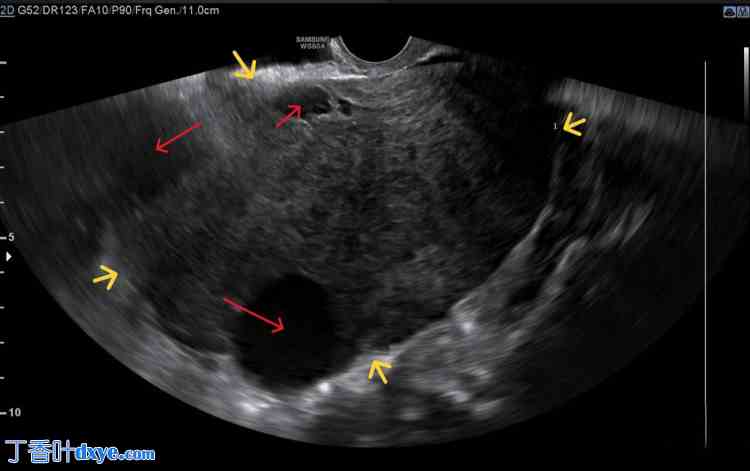

阴道检查时,发现一个大的无痛性盆腔肿块,位于道格拉斯陷凹内。经阴道超声检查显示一个边界清晰的回声肿块,包含实性和囊性成分,充满整个盆腔(图1)。

图1. 卵巢卵泡膜细胞瘤经阴道超声成像。

可见边界清晰的盆腔肿块(黄色箭头),主要为实性,并伴有少量囊性成分(红色箭头)。